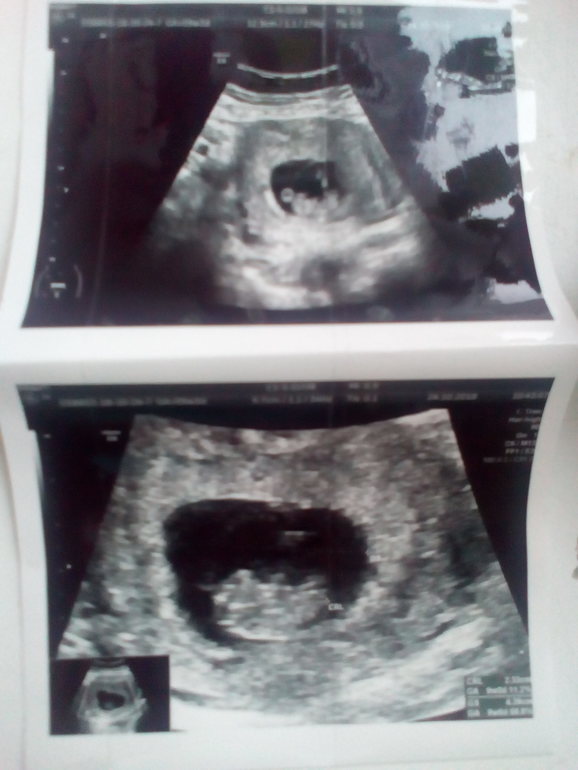

Сходила сделала УЗИ 24.10.18 г. Срок 9 недель и 2 дня, значит сейчас срок 10 недель. Как с ездим в Екатеринбург напишу.